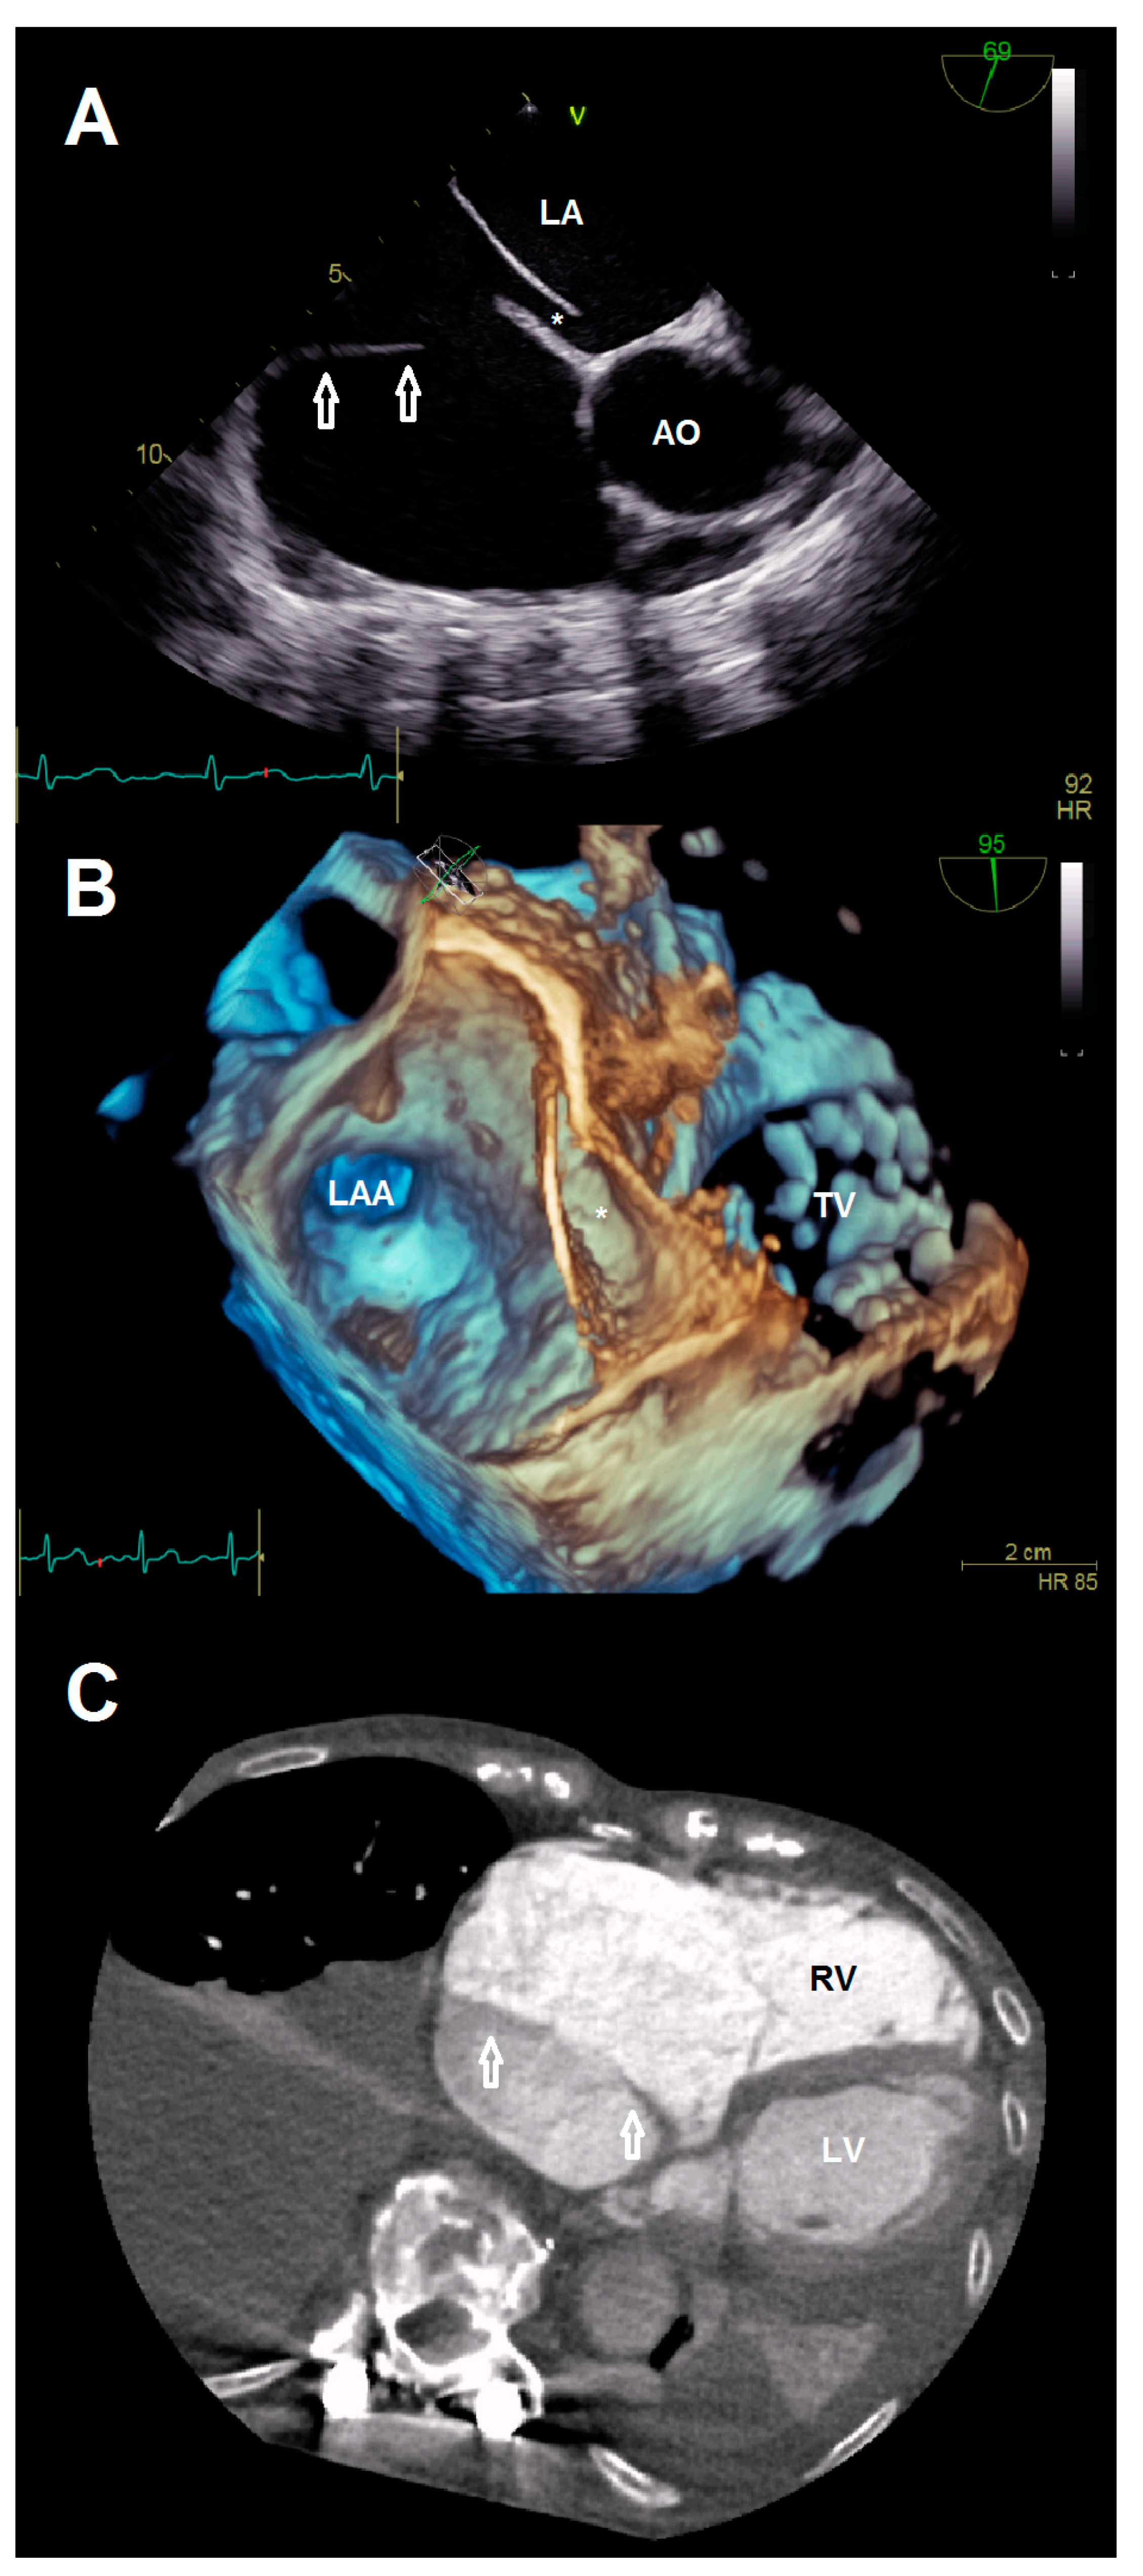

Figure 2. (A) Anatomical relationship between the additional membrane (arrows) and present patent foramen ovale (*). (B) 3-D view showing the patent foramen ovale (*). (C) Cardiac computed tomography visualizing the cor triatriatum dexter (arrows) for procedural planning. Abbreviations: AO, aorta; LA, left atrium; LAA, left atrial appendage; LV, left ventricle; RV, right ventricle; TV, tricuspid valve.

A 78-year-old female patient presented at the emergency department due to progressive dyspnea and a weight gain of 15 kg in recent weeks. Physical examination revealed massive peripheral edema and concomitant congestive dermatitis, but no jugular vein distention. Laboratory results were suggestive for diagnosis of cardiac decompensation with N-terminal pro-brain natriuretic peptide (NT-proBNP) plasma levels of 2320 ng/L, while renal function and inflammation parameters were unremarkable. As the patient was already known to have severe TR with last heart failure hospitalization one year ago, she was admitted for cardiac recompensation and evaluation of tricuspid valve intervention. Further notable medical history included permanent atrial fibrillation, iron deficiency anemia, and severe osteoporosis with previous spondylodesis and extensive oral pain therapy. Echocardiographic examination confirmed progression to massive TR (Vena contracta: 15 mm, effective regurgitation orifice area: 0.9 cm²), but also revealed an additional right atrial membrane ranging from the interatrial septum to the ostium of the IVC consistent with a CTD (Figure 1, Videos S1–S8). Application of contrast medium, as part of the bubble study, yielded an additional patent foramen ovale (PFO, Figure 2A,B; Videos S9 and S10). Besides, both atria (left atrial volume index, 109 mL/m2; right atrial volume index, 189 mL/m2), the right ventricle (right ventricular end diastolic diameter, 51 mm), and the IVC (33 mm) were severely dilated, whereas the left ventricular end diastolic diameter (46 mm) was in normal range. Right ventricular (tricuspid annular plane systolic excursion (TAPSE), 23 mm) and left ventricular function (ejection fraction, 60%) were preserved. Furthermore, liver vein congestion with flow reversal and incipient parenchymal liver disease, interpreted as cardiac cirrhosis, were identified underlining the significance of present TR (Figure 1E). Invasive coronary angiography excluded the presence of coronary artery disease, right-heart catheterization determined an isolated postcapillary hypertension (pulmonary artery pressure, 52/17/29 mmHg; wedge pressure, A-wave—20 mmHg, V-wave—23 mmHg, mean—19 mmHg). Cardiac computed tomography was conducted for the purpose of interventional planning (Figure 2C).